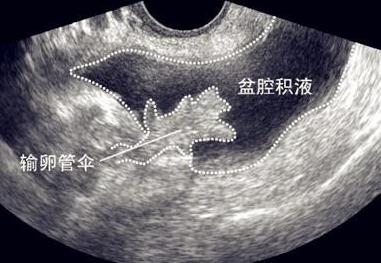

六 盆腔积液无需治疗

盆腔积液不会诱发盆腔炎等疾病,积液并不一定有害,盆腔中的积液可以为盆腔器官、肠道起到润滑的作用,少量的积液是正常生理现象。